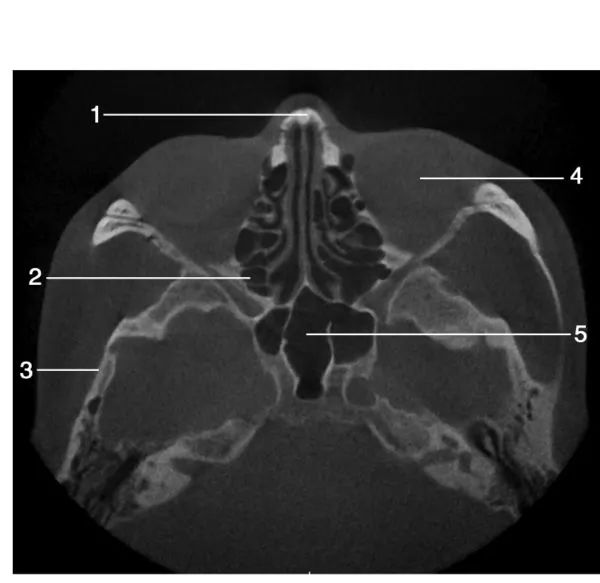

1.鼻泪管( nasolacrimal duct) ; 2.下鼻甲( inferior turbinate) ;3.上颌牙槽骨( maxillary alveolar bone) ; 4.筛窦( ethmoid sinus) ; 5.下鼻甲骨( inferior turbinate bone)